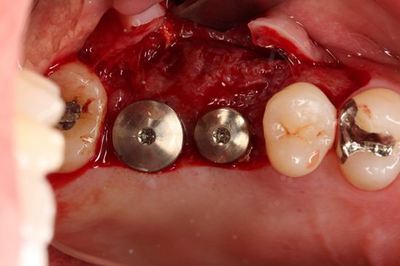

無事埋入を終えました。

挿入ジグを外しました。インプラントネックが見えています。

ヒーリングキャップのセットを終えました。

オレンジ色に見えるのは固着防止用に用いた表面麻酔軟膏です。